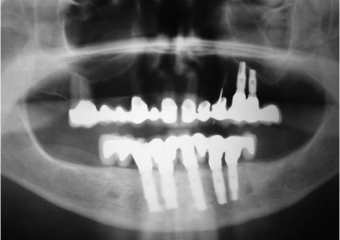

Imagem Implantes Instalados